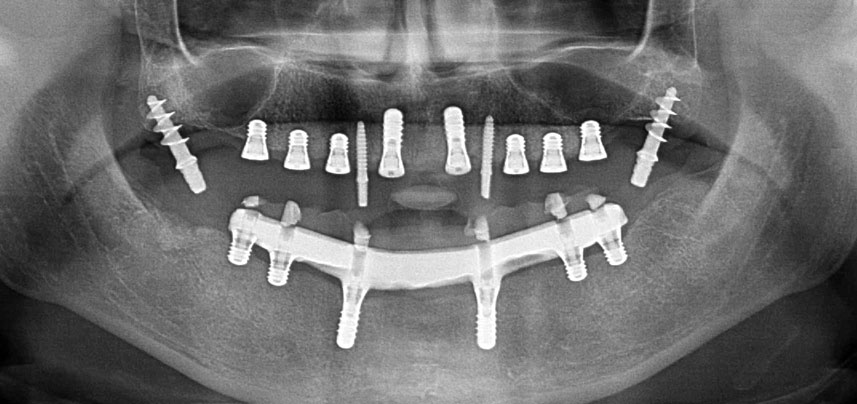

Three years later it was time for a maxillary denture of the same type. Based on CBCT planning sinus augmentation was avoided with the aid of short implants, and a surgical template was used to transfer the planned positions to the alveolar ridge (Figs. 1 and 2).

Due to the relatively hard bone (D2) in this area, the 10 mm long implant sites at positions 11 and 21 were finalized with a 4 mm diameter rotary drill, in combination with a W&H WS-75 L surgical contra-angle handpiece, the W&H Implantmed implant motor and the optional W&H Osstell ISQ module. In contrast, due to the soft bone the posterior sites were prepared to a final 3 mm diameter using the Piezomed I3P instrument. The implants were finally placed transgingivally to osseointegrate for three months (Figs. 6-10). The existing denture was retained on four provisional implants (Fig. 8).